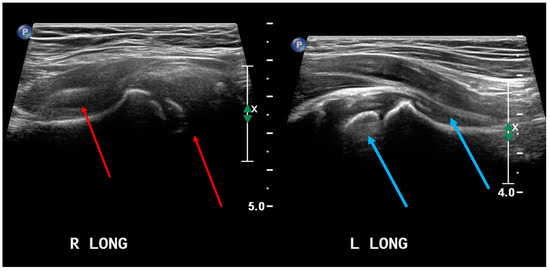

- Czyrny, Z. Osgood-Schlatter disease in ultrasound diagnostics—A pictorial essay. Med. Ultrason. 2010, 12, 323–335. [Google Scholar] [PubMed]